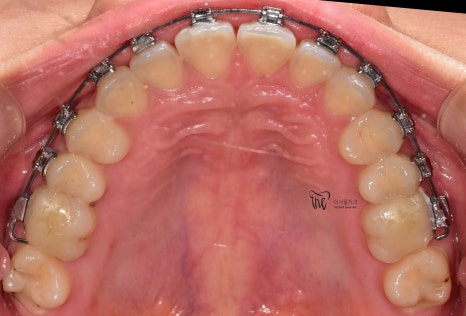

따라야 되는데 교합면 사진을 보게 되면

뭔가 전체 치열 자체는 고르게 느껴지죠?

근데, 이거 다 끝난게 아닙니다.

아직, 치아 얼라이먼트가 완성이 되지 않았습니다.

치아 얼라이먼트라는 것은 치열이 U 자 형태로

둥글게 악궁을 형성하고 있어야 되는데 살짝살짝

군데군데 아쉬운 점이 남아있습니다.

그러면서, 치아 레벨링이 완성이 되질 않았습니다.

레벨링 이라는 것은 위, 아래 치아들을 동시에

놓고 봤을 때의 가지런함을 뜻합니다.